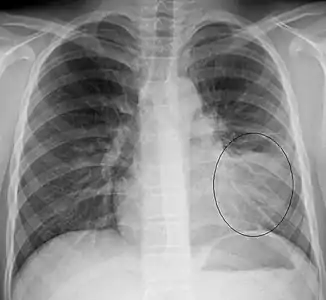

Right upper lobe pneumonia as marked by the circle.